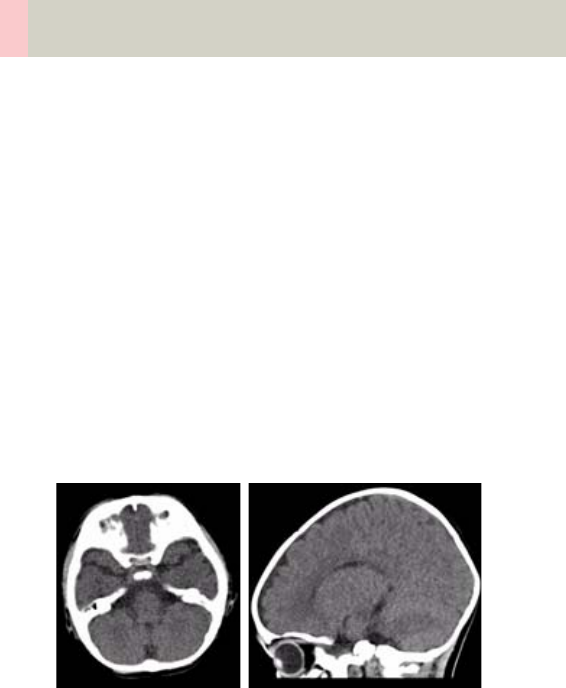

Neuro Modes

In addition to the standard collimations, the SOMA-

TOM Emotion 16-slice configuration provides a special

mode which is optimized for Neuro applications. Excel-

lent low contrast and detail resolution are achieved.

For spiral scans 4 x 0.6 acquisition mode is provided in

the range of the cerebrum. This approach shows a min-

imized partial volume effect, i.e. low level of artifacts

in the base of the skull or near vertebral bodies, as

0.6 mm detector rows are used and the narrow colli-

mation reduces scattered radiation.

One scan protocol is predefined for adults:

– HeadNeuro using an acquisition 16 x 0.6 mm in the

base and an acquisition of 4 x 0.6 mm in the cere-

brum

We recommend using this special protocol for dedi-

cated Neuro examinations.

For fast standard examinations such as rule out of

hemorrhage or ischemia, the "Routine" protocol should

be used.